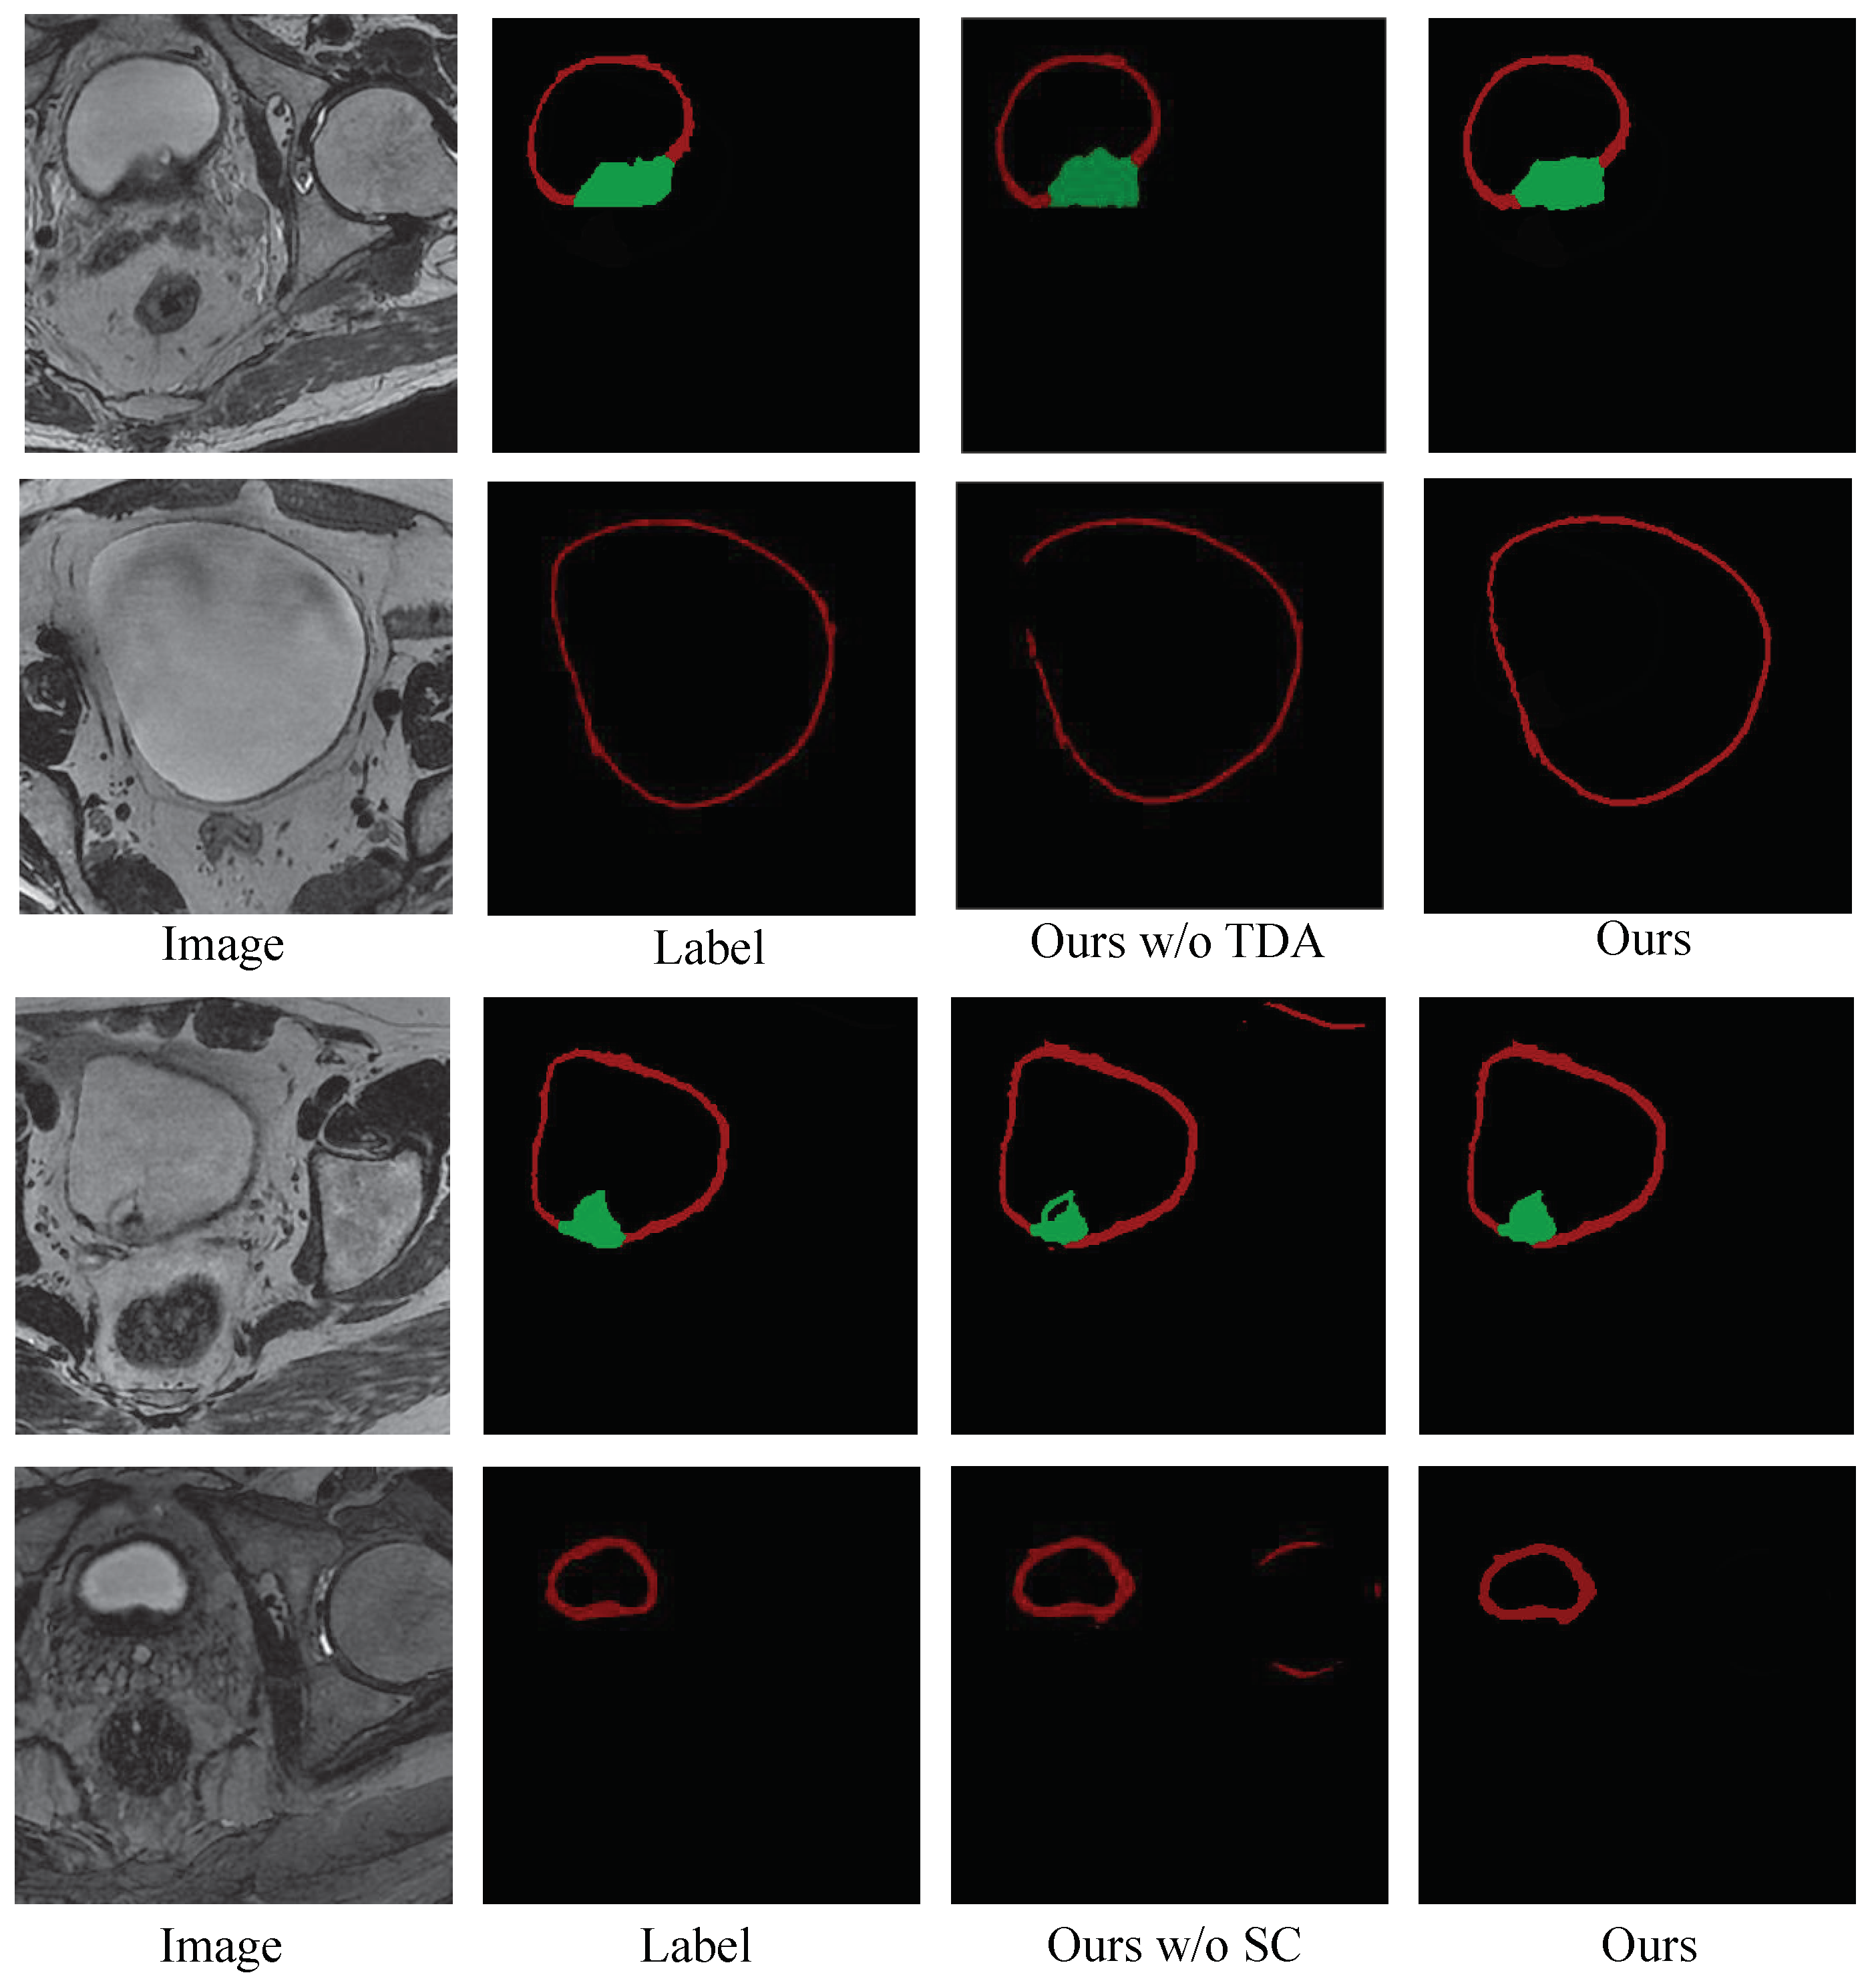

The Ablation Study of Post-Processing: To verify the effectiveness of the post-processing, we conducted ablation study experiments on our model with and without post-processing techniques. The mean DSCs of our model with different settings are given in Table 1, which shows the impact of the post-processing techniques on enhancing accuracy for bladder tumor and wall segmentation. Figure 7 shows the visualization segmentation results of our model with and without post-processing. These results show that (1) using the test time augmentation strategy or segmentation correction strategy improves the performance of the model; (2) incorporating all the post-processing techniques into the model leads to a further performance gain.

The Ablation Study of Self-supervised Pre-training: To validate the effectiveness of this self-supervised pre-training strategy, we compared the performance of the proposed method trained with and without the self-supervised pre-training. The DSC scores calculated from the results of the bladder wall and tumor segmentation are listed in Table 2 and show that the segmentation accuracy for both the bladder wall and tumor was improved after using the self-supervised pre-training strategy.

To validate the efficacy of our proposed method, we conducted a series of comparative and ablation experiments. The quantitative and qualitative results in Table 1 and Figure 7 highlight that post-processing techniques play an observable role in maintaining the structural integrity of segmentation results and the uniqueness of the bladder wall. Table 2 and Figure 8 demonstrate the accuracy and robustness of our method via implementing a five-fold cross-validation. Meanwhile, Table 3 shows that the proposed method performs well across different training data ratios when using the pre-training strategy, while Figure 9 reveals that the bladder wall is enhanced during the process of self-supervised learning. These results indicate that the proposed method achieves excellent performance in segmenting bladder walls and tumors while minimizing dependence on annotated bladder data. The improved segmentation accuracy achieved by our proposed method can lead to more reliable medical decisions, potentially improving patient outcomes and reducing the need for unnecessary interventions.

Figure 7. Visualization segmentation results with and without the post-processing strategy. The red area represents the bladder wall, and the green area represents the bladder tumor. TDA: test data augmentation; SC: segmentation correction.